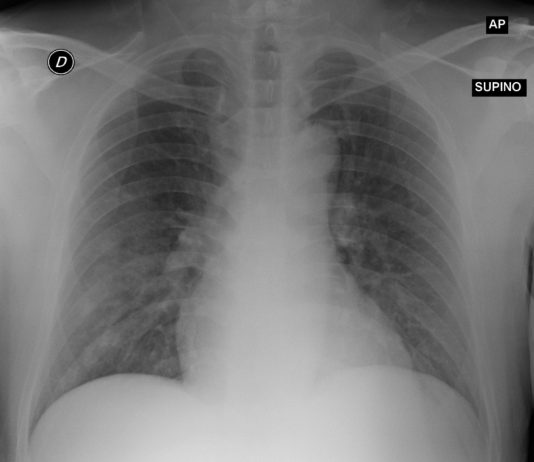

R. Bonacini, G. Besutti, P. PattaciniRadiologia IRCCS Reggio Emilia; Direttore Pierpaolo Pattacini

63-year-old male with fever, pharyngalgia asthenia and diarrhea for 5 days. Blood test: C-PR 16.27 mg/dl, procalcitonin and CBC unremarkable. Medical history: Obstructive sleep apnea syndrome.

Chest radiography: